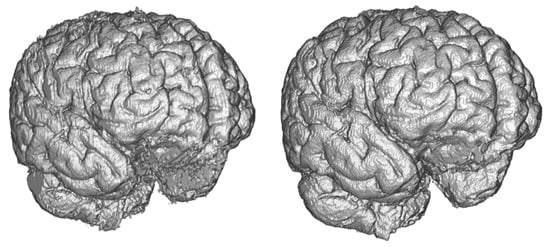

Figure 8.

Comparison of ground truth brain model (left) and brain model segmented by Dense-U-Net (right) after the final phase of training.

The Dense-U-Net network was trained in the fine-tuning phase (99 epochs) and validated using 3-folds cross-validation. In all five metrics the results are more accurate than a human expert. Output of the segmentation is visualised in Figure 8. It is clearly visible, that the proposed segmentation output overcame the human results and also results of older methods not based on deep neural networks such as the FSL. The network was able to learn the input image features as well as to generalize the brain segmentation problem. All the evaluations were made using data independent to training and the validation data.